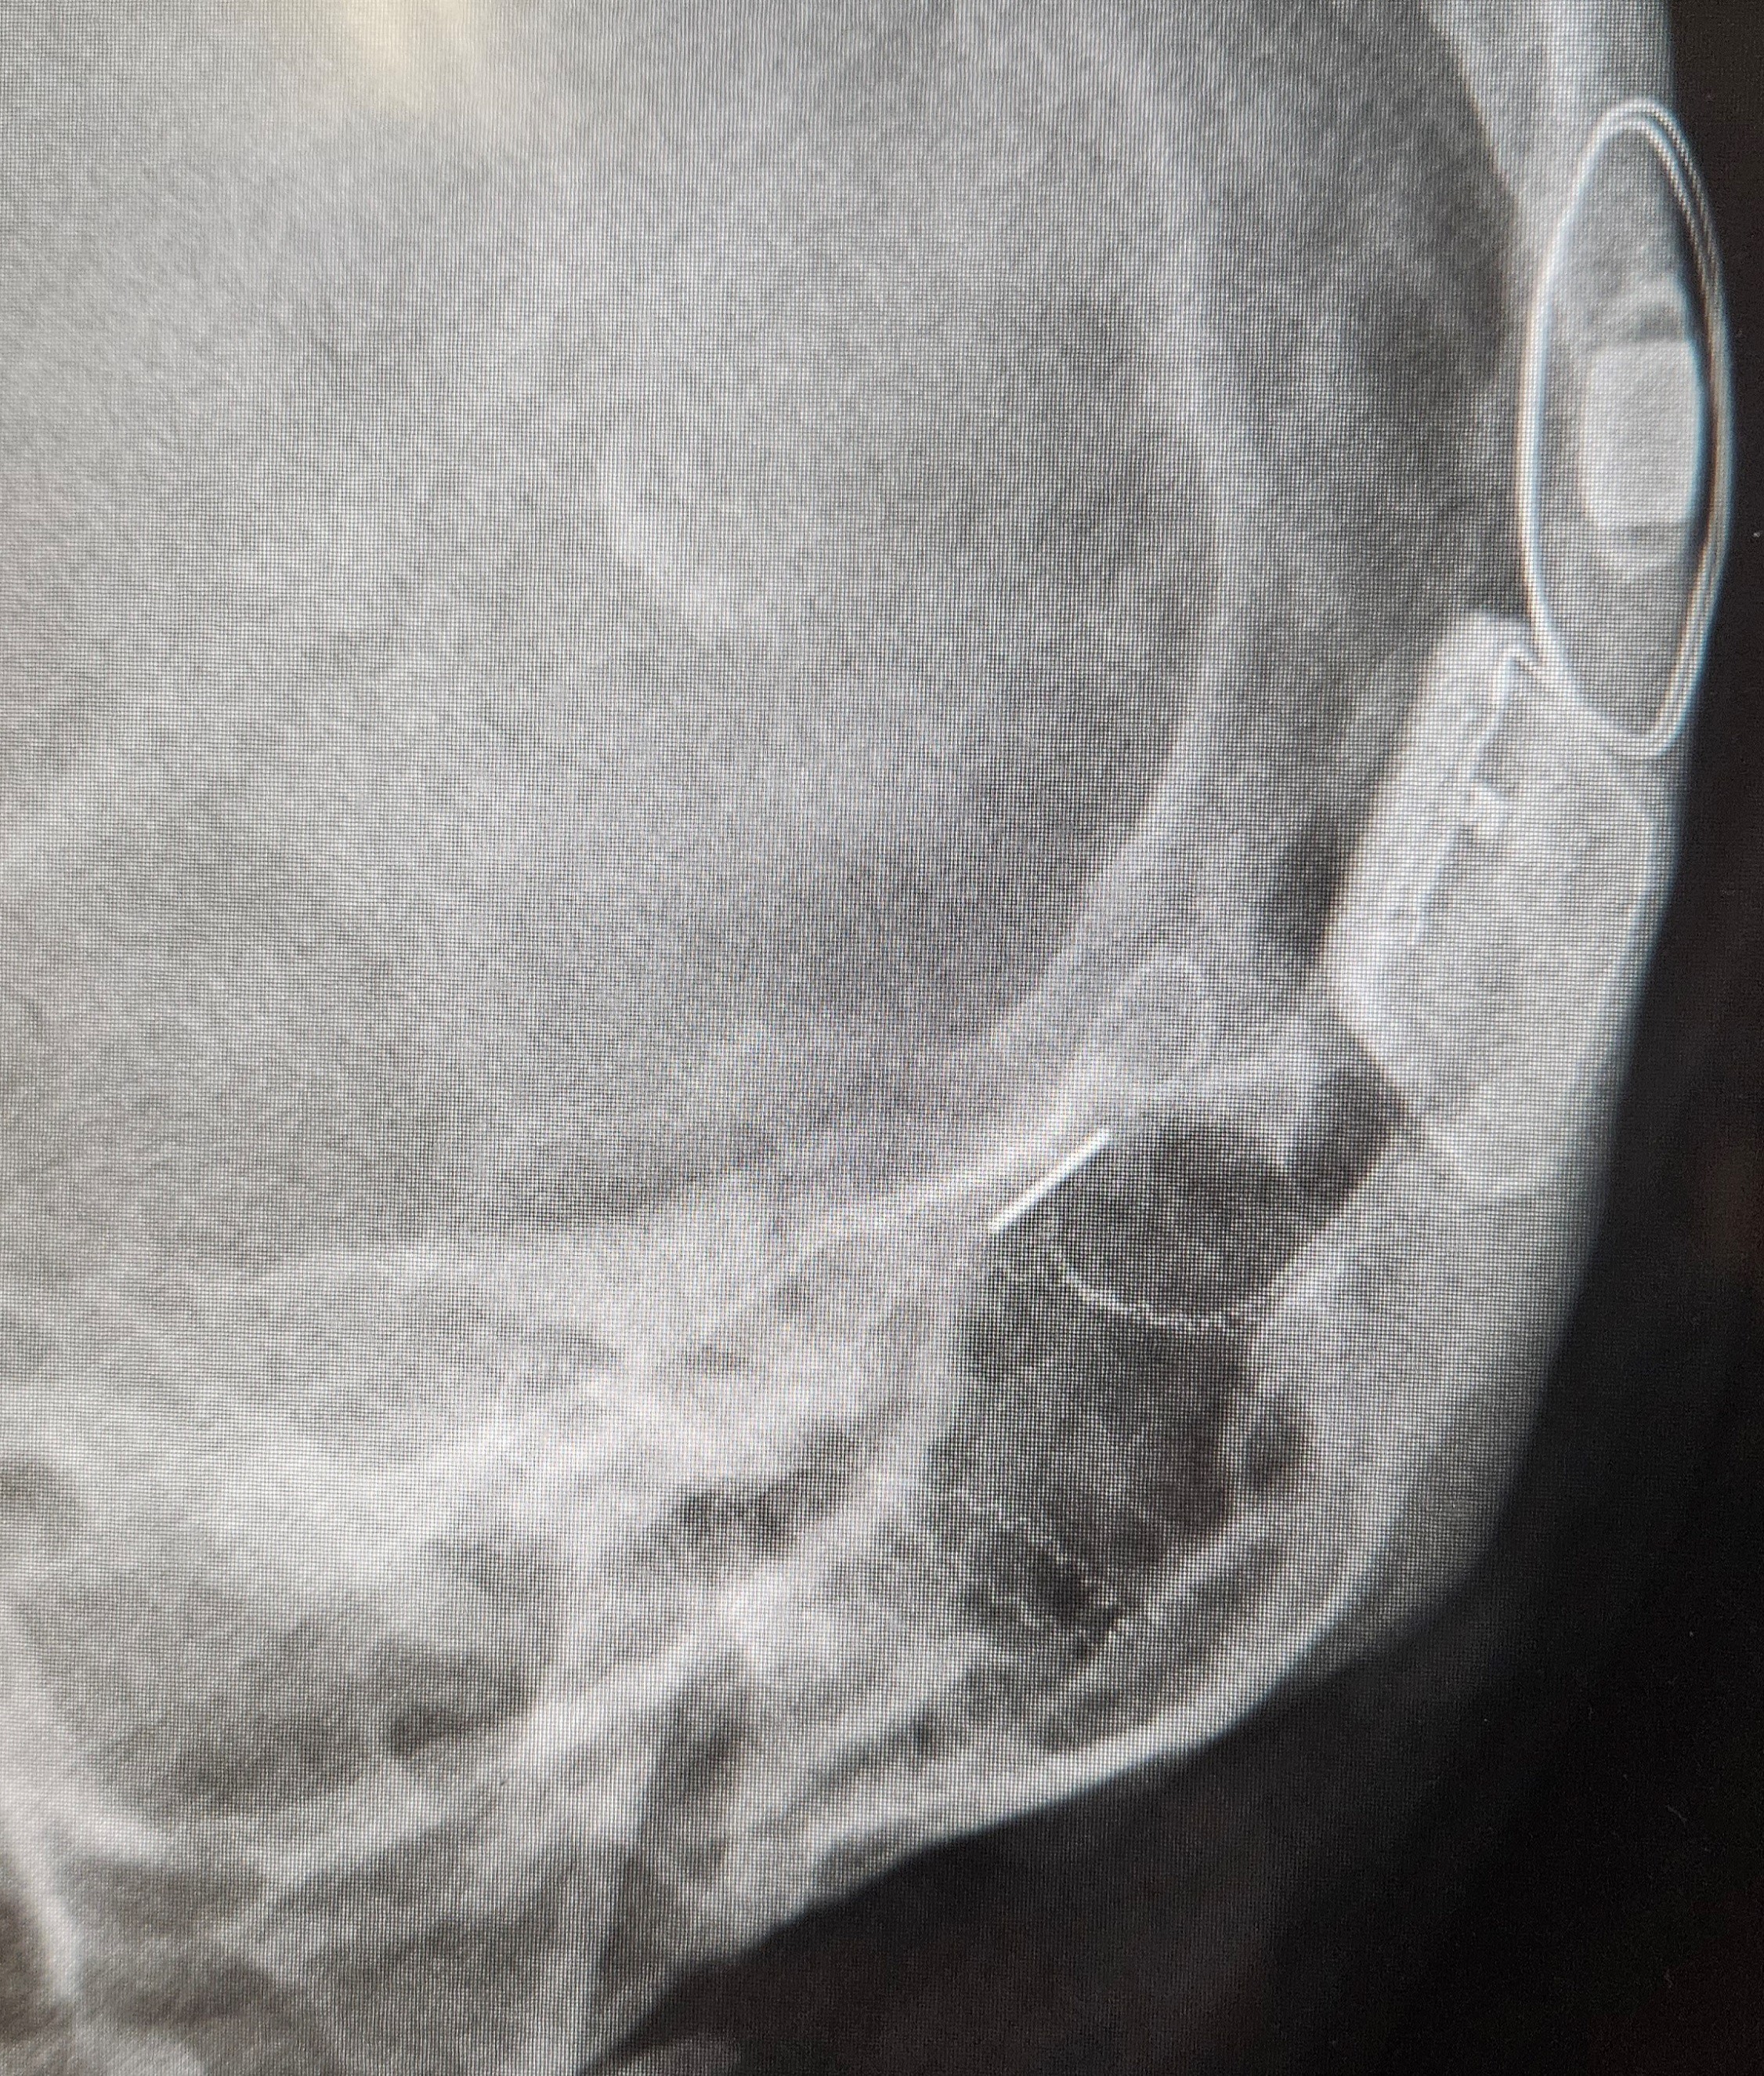

Zum Glück haben wir hier in Oldenburg eine HNO-Klinik mit angebundenem CI-Zentrum, in dem ich mich im Sommer vorstellte. Ich war eine Patientin, bei der die Indikation nicht zu 100% eindeutig war. Ich war motiviert und wollte mich von meiner Entscheidung nicht mehr abbringen lassen. Erst als ich dem Chefarzt ein selbst gezeichnetes Audiogramm mit all meinen Hörtests zeigte, war die Prognose eindeutig. Denn die Hörkurven sind von Jahr zu Jahr immer schlechter geworden. Auch neue Einstellungen und regelmäßige Upgrades brachten mich nicht weiter.

Also wurde ich am 05. Januar implantiert. Alles verlief bestens und ich hatte kaum Nebenwirkungen oder Begleiterscheinungen. Die erste Woche nach der Erstanpassung hörte ich nur monotone Morsezeichen. Tägliches Hörtraining mit einem Programm, welches von der Klinik entwickelt wurde. Zahlen, Wörter, Sätze, Wortpaare. Fünf Wochen nach der OP habe ich die ersten Wörter verstanden. Die Audiogramme wiesen von Woche zu Woche ein immer besseres Sprachverstehen auf: 45%, 55%, 70%, 85%. Acht Wochen nach der OP wollte ich endlich wieder arbeiten, da mir zu Hause allmählich die Decke auf den Kopf gefallen ist. Im März besuchte ich die Selbsthilfegruppe in Oldenburg. Der Altersdurchschnitt der Teilnehmerinnen und Teilnehmern lag bei ca. 65 Jahren. Der Austausch tat gut, nichtsdestotrotz suchte ich nach Leuten, die genau wie ich den Arbeitsalltag bestreiten und täglich im Störschall klarkommen mussten. Eine solche Gruppe gab es also noch nicht. Ich sehnte mich nach Gleichaltrigen.